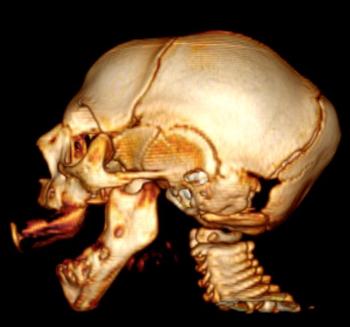

In a third study, ultrasound and fetal MRI were performed on pregnant patients with Zika virus infection at different gestational ages. Once the babies were born, they underwent ultrasound, CT and MRI. The researchers then created 3-D virtual and physical models of the skulls. More than half the babies had microcephaly, brain calcifications and loss of brain tissue volume, along with other structural changes.

"The emergence of Zika virus in the Americas has coincided with increased reports of babies born with microcephaly," said study author Heron Werner Jr., M.D., Ph.D., from the Department of Radiology at Clínica de Diagnóstico por Imagem. "An early diagnosis may help in treating these babies after birth. Moreover, the knowledge of abnormalities present in the central nervous system may give hints about the pathophysiology of the disease."